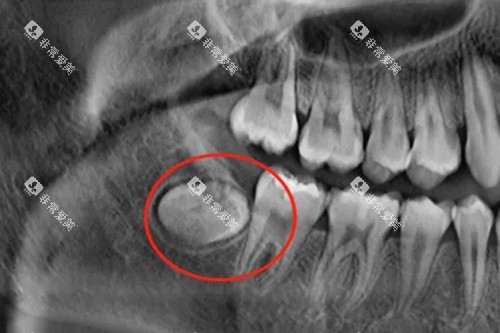

埋伏智齿:骨内埋伏的高难度收费标准

埋伏智齿完全隐藏于牙槽骨内,需通过影像检查定位,手术涉及切开牙龈、大量去骨及精细分离,是拔智齿中难度更高的类型,收费也处于更高区间。

低位埋伏智齿:1500-2500元起

牙齿深埋于牙槽骨底部,可能邻近下牙槽神经,需借助锥形束CT正确定位,手术风险较高,收费包含神经保护相关操作成本。

完全骨埋伏智齿:1800-3000元起

牙齿完全被骨组织包裹,无任何暴露部分,手术需大面积去骨并分割牙齿,部分病例需采用超声骨刀等特殊设备,进一步推高了收费。

钦州本地这类高难度手术的收费中,设备使用成本占比约30%,医生经验带来的技术溢价也较为明显,这也是不同机构间价格差异的重要原因。